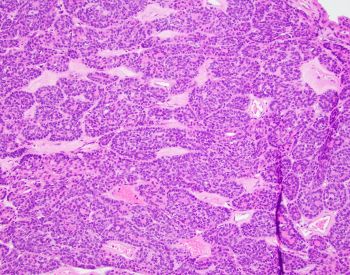

A 40 y/o euthyroid female and a 3 cm left-sided thyroid nodule incidentally found.